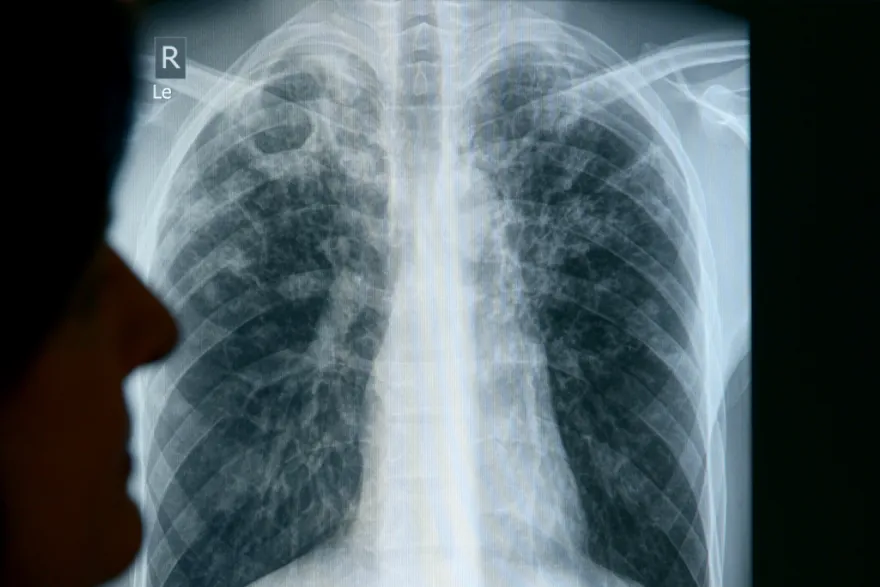

- Az esetek többsége — nagyjából 70–80 % — tüdő-tuberkulózis, de előfordulhatnak úgynevezett extrapulmonális (nem tüdőt érintő) esetek is.

- Ha valaki TB-gyanús tüneteket tapasztal (hónapokon át tartó köhögés, vérköpet, láz) → forduljon orvoshoz, és kérje a szükséges vizsgálatokat (röntgen, köpetvizsgálat, labor).